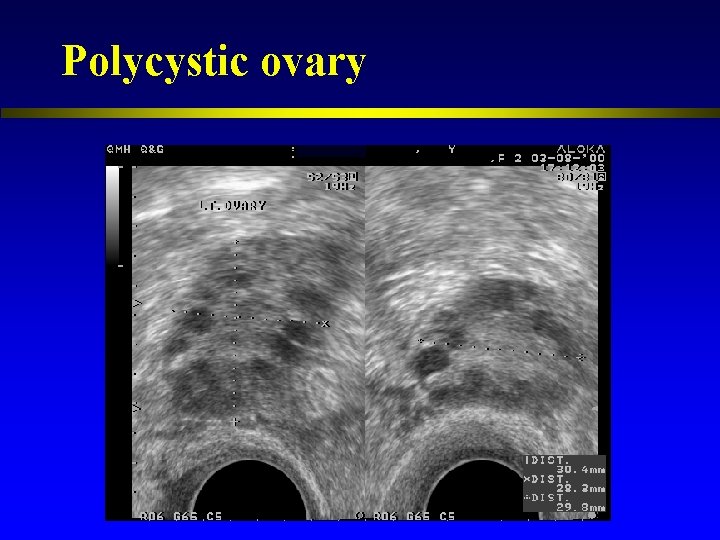

Polycystic ovary

Polycystic ovary: international consensus definitions 1. 2. 12 follicles of 2 -9 mm in diameter in at least one ovary or Increased ovarian volume (>10 cm 3) (Balen et al. , 2003)